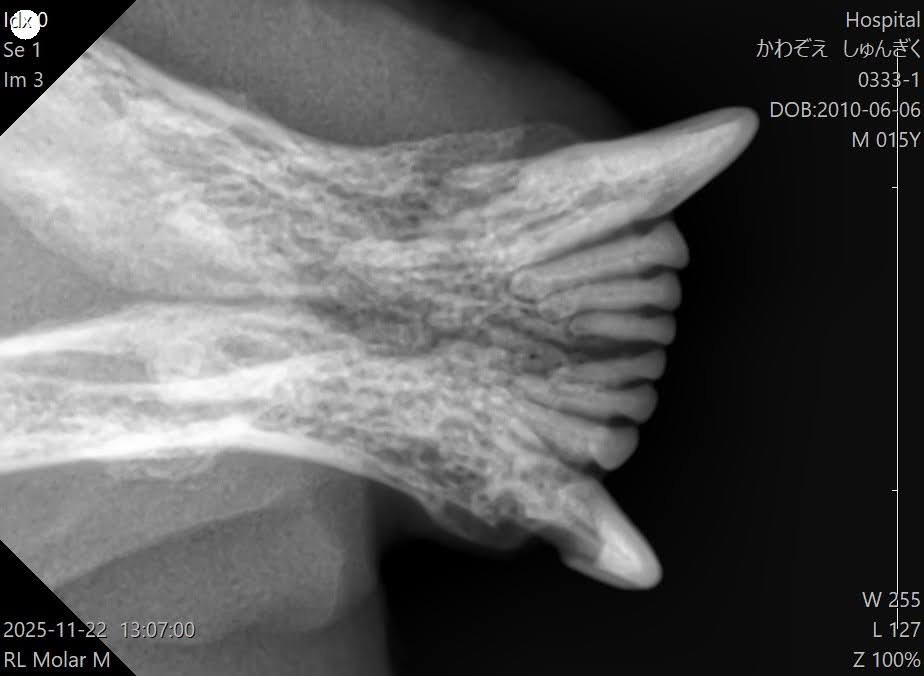

歯科専用レントゲン撮影した猫ちゃんの症例だたとえば、今日の歯科の勉強会のタイトルは口内炎!

こんな風に、一本一本評価しないと

口が赤い!だけでは、診断が難しいのです。